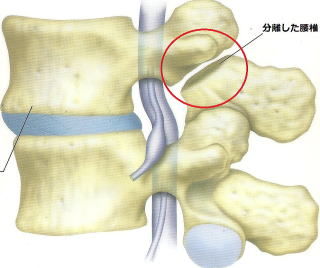

ブログ  治療の解説

治療の解説  ブログ